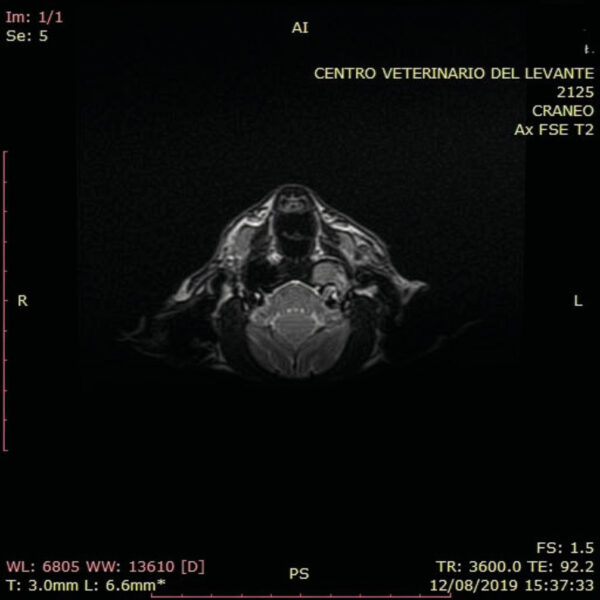

La resonancia magnética (RMN) permite una mejor visualización de los tejidos blandos y de las estructuras del oído interno, resultando útil en la diferenciación de la enfermedad vestibular central frente a la periférica.

Al igual que en la TC, el paciente se coloca en decúbito esternal con la cabeza en la bobina de radiofrecuencia y las extremidades anteriores orientadas hacia caudal. Se pueden usar los mismos puntos de referencia que en la TC para facilitar el posicionamiento.

La RMN de otitis media muestra material de intensidad de señal intermedia en la bulla timpánica en las imágenes ponderadas en T1 e hiperintensidad en las imágenes ponderadas en T2. Tras administrar un agente de contraste, puede observarse un realce del margen interno en T1. En imágenes ponderadas de T2, una apariencia laminada de intensidades de señale alta y baja sugiere cronicidad, representando las zonas hipointensas tejido fibroso (imagen 9). Los cambios óseos leves de la bulla timpánica son difíciles de valorar por RMN.